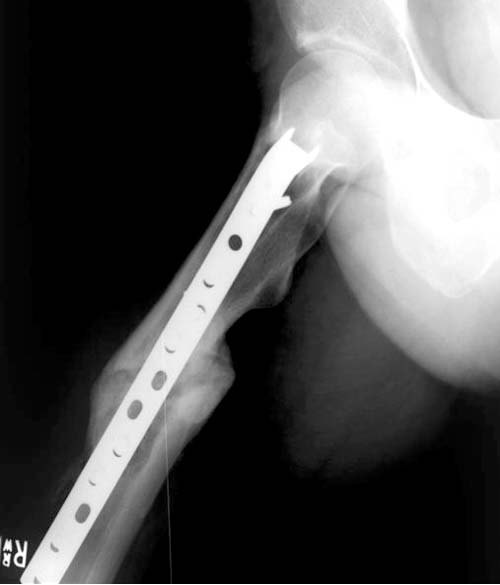

Имя     : 3 Fem nonunion postop.jpg

Тип     : image/jpg

Размер  : 34872 байтов

Описание: отсутствует

Url     : http://weborto.net:8080/pipermail/ortho/attachments/20111214/0c6bb1fc/attachment-0006.jpg

Для решения проблемных состояний некоторые коллеги выбирают только малоинвазивные методы, забывая другие методы лечения. Желание восстановить малоинвазивно это хорошо, но если имеется возможность полного восстановления  открытым методом - надо использовать. Вылеченный ложный сустав лучше, чем повторение процедур по поводу несостоятельности Гамма гвоздя...

С суждением, что "гвоздь внутри канала действует как внутренний протез даже без сращения кости" можно согласиться в некоторых состояниях, для короткого времени, например, в онкологии. А так - современный ортопед должен владеть всеми видами реконструктивной хирургии, включая открытые.

Поэтому хотел предложить альтернативную технику, открыть место ложного сустава субвастус доступом и кортикотомия, одномоментное удлинение, аппозиция латерального кортекса. Для фиксации Blade Plate с коротким клинком при возможности или обычная прямая преконтурированная 4.5 мм пластина с медиальным костным графтом.

По-моему, такая простая техника решит проблему склерозированного старого ложного сустава намного дешевле, чем гвоздь, и без необходимости обьязательного ЭОПпри установке Гамма.

Надеюсь, мои опасения окажутся чрезмерными, и Вы покажете правильно установленную Гамму, и успешный результат лечения.